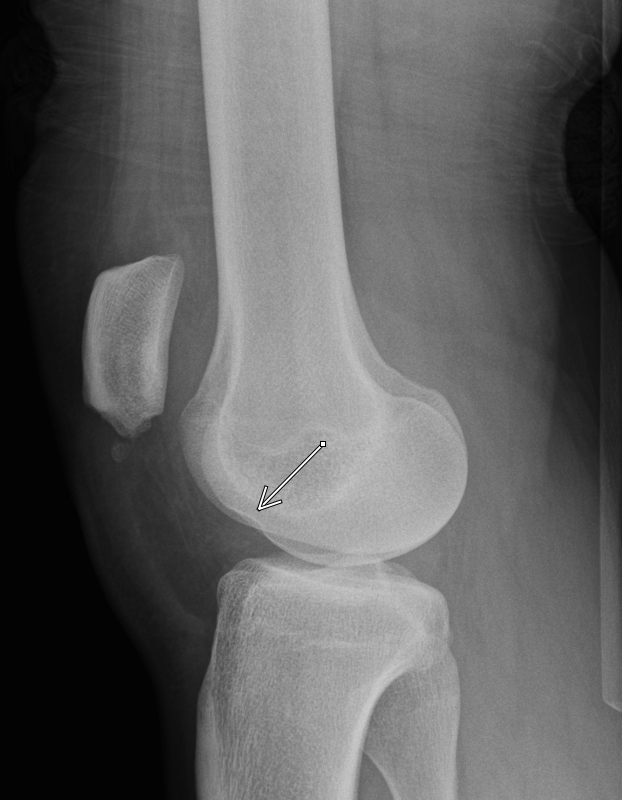

Occipital condyle avulsion fracture is often difficult to see on sagittal images

#radres always look on coronal and axial images, add this to your checklist#radiology#spine@NASSspine#EMRAd#FOAMed#spinetrauma#injurypic.twitter.com/lC7l73mnEj